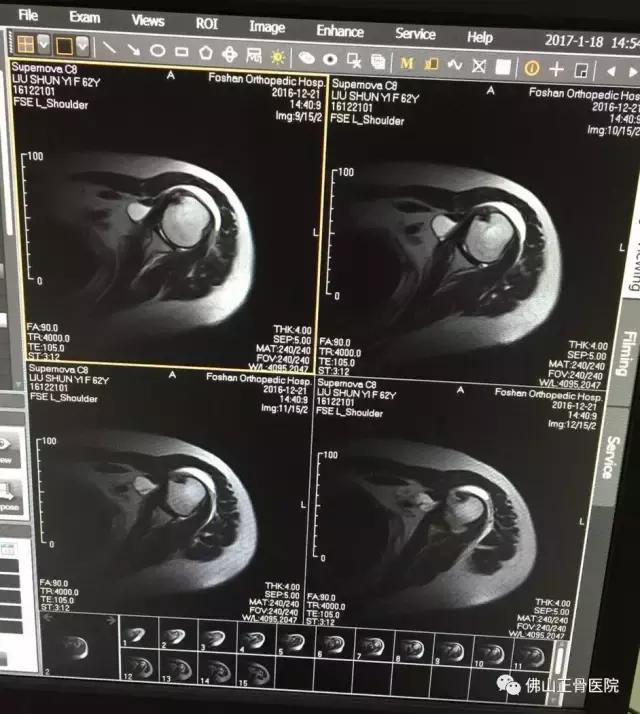

MR示:患者左肩关节改变,冈上肌肌腱撕裂,左肩关节腔内有积液,右下盂唇前方有少量积液,诊断为肩袖损伤。

62岁的刘女士,家住广州。2015年12月中旬,在家中跌倒后出现了左肩剧痛,左臂上举困难。疼痛严重时不能左侧卧位,明显影响睡眠和穿衣等日常活动,到了医院拍X检查,寻找受限原因,却没有发现“骨质异常”,通俗地说,就是没有伤到骨头。

原来困扰刘女士的症状为左肩袖损伤。在超声仪器下,曾主任看见了刘女士肩膀下面的肌腱撕裂和积液,确诊病因后,他随即为刘女士做了超声介导下注射治疗。后经综合治疗2周后,刘女士左肩疼痛基本改善,穿衣等日常活动也恢复正常。